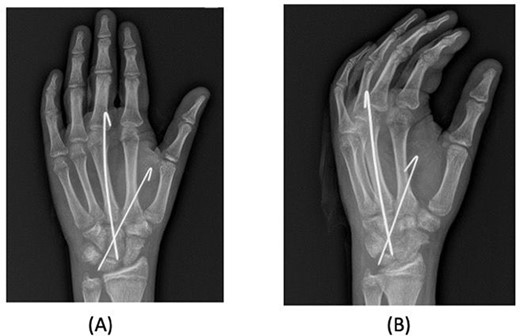

A 15-year-old boy, right handed, was not known to have any chronic medical illnesses. He presented to the emergency department (ED) with a history of severe left-wrist pain and swelling after falling from a height of 5–6 meters on an outstretched hand with the wrist in extension three hours prior to the ED presentation. The pain is mainly located in the left wrist’s dorsum and distal part of the forearm. Increasing pain with movement and relived with immobility. On examination, a normal-appearing wrist. No open wounds or lacerations, nor abrasions. There is no obvious deformity. There was mild swelling in the wrist. Tenderness over the dorsal radial wrist, including the anatomical snuff box. The range of motion was restricted due to pain. The neurovascular examination was normal. A plain radiograph in the ED showed a scaphoid tubercle fracture and a capital bone fracture. Initial radiographs are shown in Fig. 1). The patient was taken for computerized tomography (CT) to better define the extent of the injury (Fig. 2). A CT scan showed a displaced fracture of the capitate carpal bone, with an avulsion fracture at the distal tubercle of the scaphoid carpal bone, with extension to the articular surface. In addition to perilunate fracture, the rest of the carpal bone’s alignment is maintained. The patient was shifted to the operating room for open reduction and k-wire fixation of the scaphoid and capitate fracture of the left hand. Under general anesthesia, a tourniquet was applied. The incision was over the dorsal aspect of the left wrist, proceeding with the wrist capsule opening. The fracture was fixated with two Kirschner wires. Alignment was assured intraoperatively with an x-ray (Fig. 3). Plain radiographs post-fixation showed intact alignment. Postoperatively, the wrist was immobilized in a long-arm splint. The Kirschner wires and the protected splint were removed at 5 and 8 weeks, respectively. Immediately afterward, physiotherapy started. A few months following surgery, the site of the fracture healed radiologically. The patient had no pain, and the range of motion was acceptable after a period of physiotherapy. Figure 4 demonstrates a medical illustration of a scaphocapitate fracture.

Posteroanterior and oblique radiographs taken intraoperatively after fixation, demonstrating proper alignment of hardware.